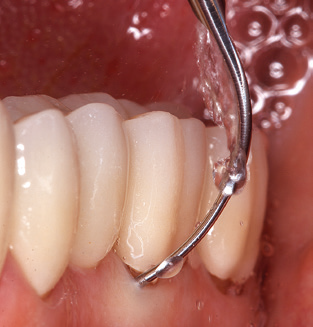

Of course, working tips for the cleaning of implant surfaces are also indispensable for SPT in patients fitted with implants. The implant cleaning attachment on the system used here is characterised by its tapered, hexagonal design. This design allows light, atraumatic penetration of the peri-implant pocket and displays a good cleaning performance (Fig. 7).